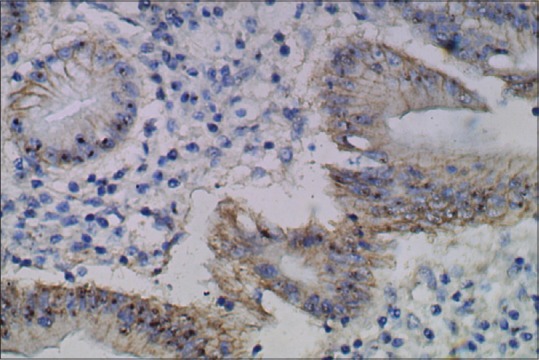

Immunohistochemistry for HER2/neu showed a score of 3+ positivity [Figure 3] in 8 cases (17.1%), all were adenocarcinoma of intestinal variant having well and moderate differentiation [Tables [Tables22 and and3]3] and originated from the body and pyloroantrum (four each). HER2 score was 2+ [Figure 4] in 7 cases (14.9%) these were again well to moderately differentiated adenocarcinoma of the intestinal variant. HER2 score was 1+ or 0 [Figure 5] in 32 cases (68.1%). In this group, 13 cases (40.6%) were graded as poorly differentiated, and among them eight cases were diffuse variant of adenocarcinoma. Only two cases of poorly differentiated, one of moderately differentiated carcinoma of intestinal variant and four cases of well-differentiated carcinoma showed 2+ HER2 positivity. Well and moderately differentiated carcinoma showed more HER2 3+ positivity (8 cases, 25%), whereas cases of poorly differentiated carcinoma predominantly (86.7%) showed the lack of HER2 expression. HER2 positivity score of 2+ was noted in seven cases of Stage III disease, whereas score 3+ was noted four cases each of Stage III and Stage IV disease, respectively. HER2 score was analyzed according to the grade of adenocarcinoma [Table 4]. A score of 2+ or 3+ was noted in 13 (40.6%) cases of well and moderately differentiated carcinoma but none in poorly differentiated carcinoma.

| Figure 4:Well-differentiated adenocarcinoma showing human epidermal growth factor receptor 2 score of 2+ (human epidermal growth factor receptor 2 immunostain, ×400)